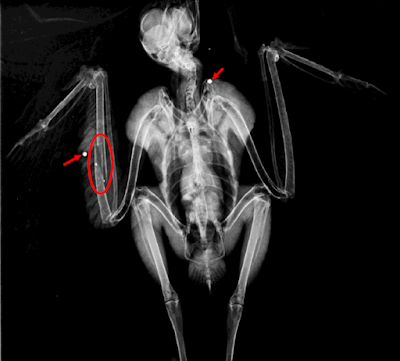

Este é mais um caso de abate ilegal de espécies da nossa fauna. Uma águia-d’asa-redonda ingressou com uma ferida circular na asa e com um hematoma.

Ao realizar-se um raio-x foi possível confirmar a presença de dois chumbos, um na asa e outro no ombro (setas). Confirmou-se ainda uma fractura no cúbito direito (círculo).